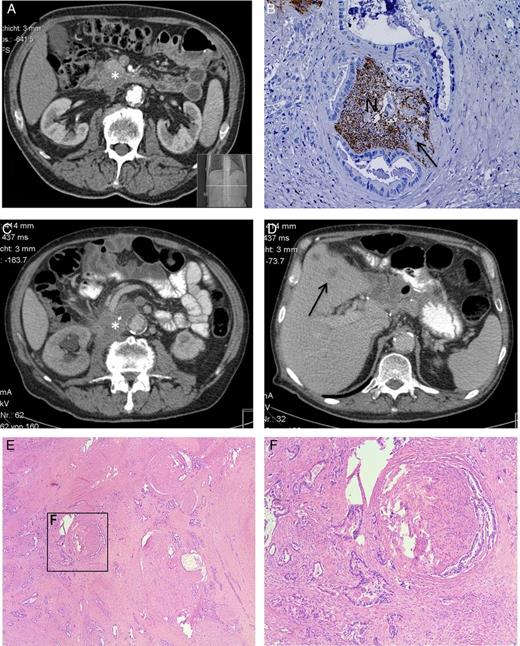

A 67-year-old male patient with severe lumbar back pain and weight loss was primarily treated in a community hospital. The preoperative CT scan showed a suspicious mass in the pancreatic head, without any evidence for extrapancreatic tumor manifestation (Fig. 1A). An explorative laparotomy was performed by the local surgeon and the tumor was classified as locally not resectable. A tumor biopsy was taken and a palliative gastroenterostomy was performed. The histopathological analysis revealed a poorly differentiated ductal adenocarcinoma of the pancreatic head. After the primary operation, the patient was referred to our center. As the tumor was judged borderline resectable, our interdisciplinary tumor board recommended ‘neoadjuvant’ chemotherapy with Gemcitabine/Oxaliplatin for 10 cycles. Restaging after the complete neoadjuvant therapy showed local tumor regression without evidence of distant metastasis. Therefore, a pancreatoduodenectomy (Whipple's operation) was subsequently performed. The histopathological examination showed an ypT3, N0 stage, Grade 3 tumor. The dorsal resection margin revealed an R1 resection, and the resected specimen revealed severe intrapancreatic NI by cancer cells (Fig. 1B). In the postoperative period, the strong pain sensations disappeared completely 2 weeks after tumor resection. With postoperative pancreatic enzyme supplementation, the patient experienced slight weight gain. At this time, an additive chemotherapy with Gemcitabine was initiated. Five months postoperatively, the patient had no pain, but suffered from mild polyneuropathy of hands and feet due to the side effects of the neoadjuvant treatment. Seven months after resection, the patient developed severe lumbar pain which again required the hospitalization of the patient. The performed CT scan showed local tumor recurrence around the inferior vena cava and liver metastasis (Fig. 1C and D). The chemotherapy regimen was changed from Gemcitabine to 5-Fluoruracil and a symptomatic adjunct analgesic therapy with Pregabalin was initiated in addition to Metamizol, which led to a short-term pain relief. However, 4 weeks later, the pain syndrome of the patient exacerbated again and was not responsive to current pain medication. Only a CT-guided blockade of the celiac plexus enabled considerable, but only temporary pain relief. Four weeks later, the patient's condition deteriorated again, with severe recurrence of uncontrollable lumbar back pain. Only a continuous morphine infusion provided a palliative pain control until patient's death.

(A) Preoperative CT scan after the neoadjuvant chemotherapy shows the pancreatic head tumor (*). (B) Postoperative histopathological analysis shows severe NI of PCa cells (indicated by the arrow) in the nerve (N), staining: protein gene product 9.5 (PGP9.5), hematoxylin counter stain. (C and D) The CT scan shows the 7 months postoperative diagnosed local recurrence (*) and liver metastasis (→). (E and F) Postmortem histopathological analysis shows the invasion of pancreatic tumor cells in the extrapancreatic neural (here celiac) plexus.

Prior to the Whipple's operation, the patient gave written informed consent for an extensive postmortem histology analysis. The respected ethical approval was obtained from the ethical committee of the Klinikum rechts der Isar, Technische Universität München. This enabled us in this unique case, to correlate the symptoms of the patient with the postmortem histological samples from the peripancreatic local recurrence area. All samples from the retropancreatic region demonstrated large extrapancreatic nerves embedded in dense fibrotic tissue areas. Remarkably, nearly all visible nerves were infiltrated by very large clusters of cancer cells, and the neural structures were entirely destroyed (Fig. 1E and F). Hence, these fibrotic areas with severe NI represent the direct histological correlate of the increased retropancreatic signal density (hyperdensity) seen on the re-staging-CT scan.